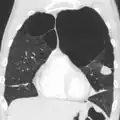

A CT scan is not routinely used except for the exclusion of bronchiectasis.[5] Pulse oximetry measurement of peripheral oxygen saturation is recommended in people with clinical signs of respiratory failure or right heart failure.[5] An analysis of arterial blood is recommended in those with a peripheral oxygen saturation of 92% or less to determine actual blood oxygen level and assess for high levels of carbon dioxide in the blood, which may have therapeutic implications such as need for non-invasive ventilation or oxygen supplementation.[10] WHO recommends that all those diagnosed with COPD be screened for alpha-1 antitrypsin deficiency.[40]

A severe case of bullous emphysema -

Axial CT image of the lung of a person with end-stage bullous emphysema -